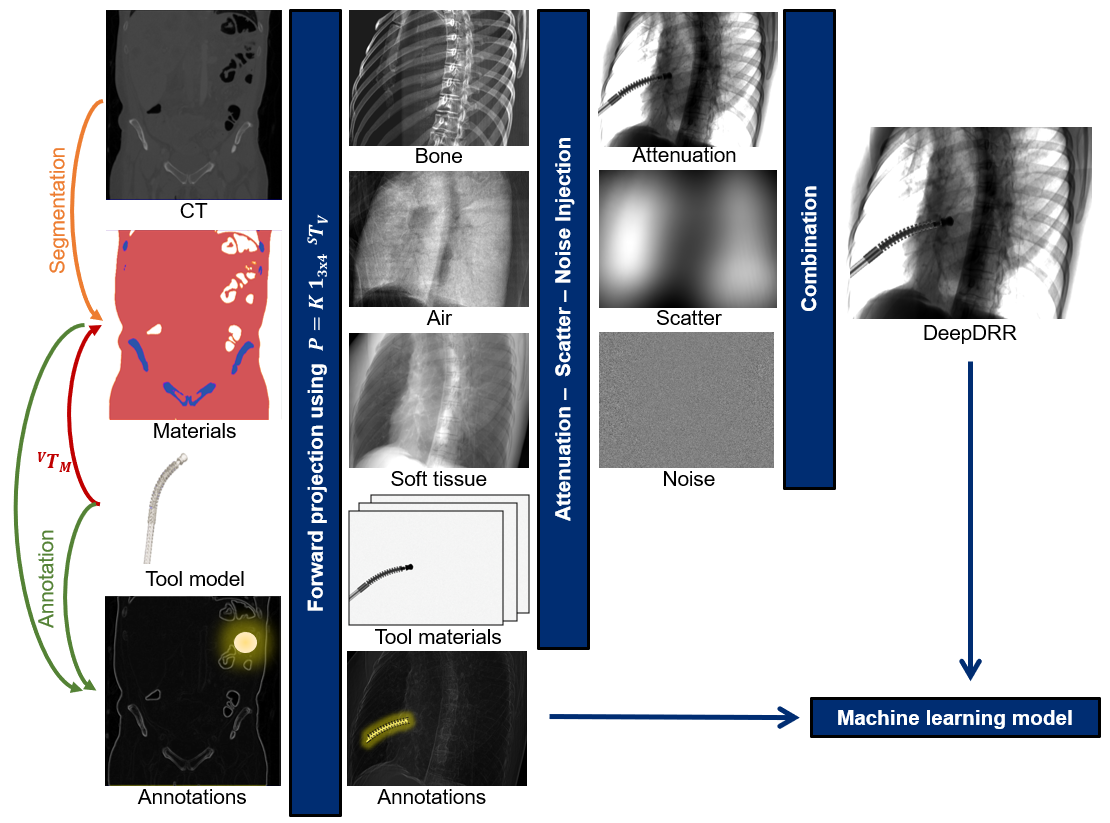

DeepDRR combines machine learning models for material decomposition and scatter estimation in 3D and 2D, respectively, with analytic models for projection, attenuation, and noise injection to achieve the required performance. The pipeline is illustrated below.

Further details can be found in our MICCAI 2018 paper "DeepDRR: A Catalyst for Machine Learning in Fluoroscopy-guided Procedures" and the subsequent Invited Journal Article in the IJCARS Special Issue of MICCAI "Enabling Machine Learning in X-ray-based Procedures via Realistic Simulation of Image Formation". The conference preprint can be accessed on arXiv here: https://arxiv.org/abs/1803.08606.